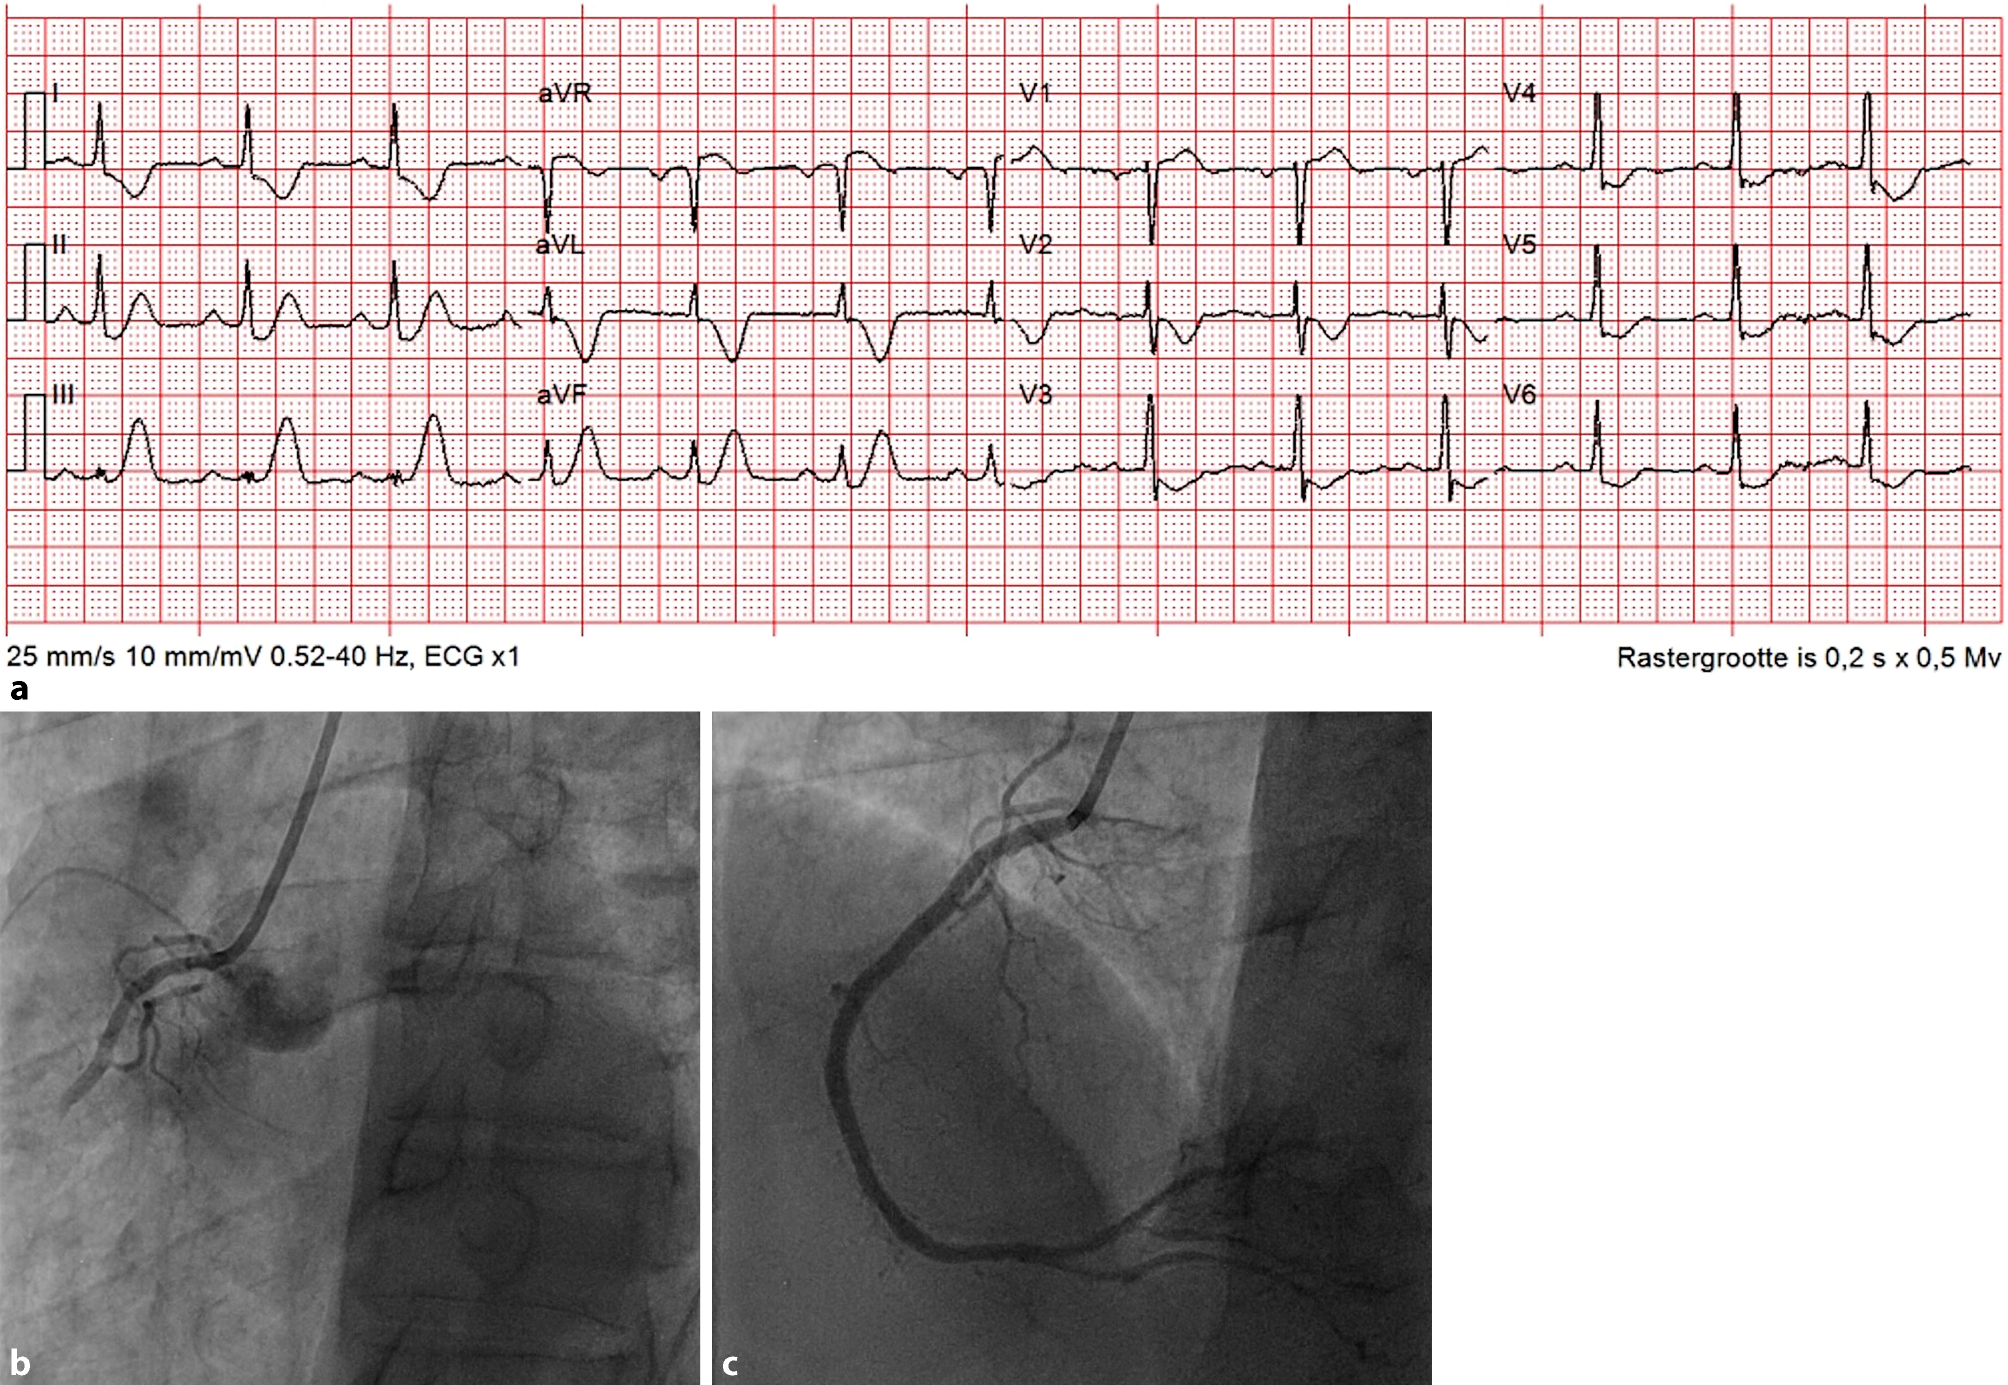

A 62-year-old man attended our emergency department with acute chest pain. The electrocardiogram (ECG) showed 2 mm ST-segment depression at the J point with tall, peaked T‑waves in inferior leads, 2 mm ST elevation in aVR and reciprocal depressions in leads I and aVL (Fig. 1a). These features resemble ‘de Winter pattern’ ECG abnormalities: upsloping ST-segment depression at the J point in leads V1–V6 with tall, positive and symmetrical T waves. This is recognised as a sign of proximal left anterior descending coronary artery occlusion, observed in a minority of patients with acute anterior myocardial infarction [1]. This ECG pattern has rarely been described in inferior ST-segment elevation myocardial infarction [2].

a Electrocardiogram at first medical contact. b Angiography showing proximal occlusion of the right coronary artery. c Angiography after primary percutaneous intervention

We performed urgent coronary angiography, showing a proximal occlusion of the right coronary artery (Fig. 1b). After primary percutaneous coronary intervention (Fig. 1c), complaints disappeared and the ECG normalised.